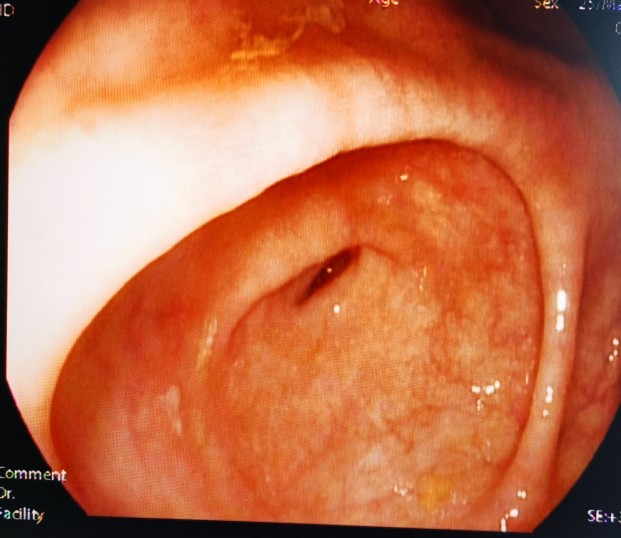

经造瘘口肠镜向下观察